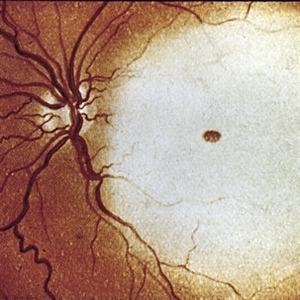

Macular hole after commotio retinae.

Condition/keywords: commotio retinae, macular hole